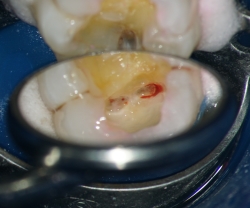

まず、ラバーダムというゴム製のシートで歯を多い、唾液や細菌感染から保護をした状態でむし歯を削り取ります。むし歯の除去の際には、切削中に歯の内部に細菌感染させないように顕微鏡下で慎重に除去していきます。このような対策を行っておくことで、たとえ神経に達した場合でも、顕微鏡で毛細血管などの組織を確認できます。

そして、残せる可能性がある神経であれば、歯髄を保護する作用のあるセメント使用し、経過を見て行きます。